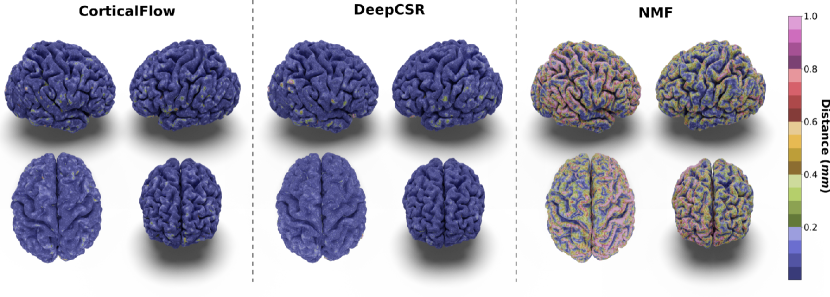

In our experiments, we noticed that CorticalFlow produces more geometrically accurate surfaces than the other methods. On average, it presents better geometric metrics across all the cortical surfaces. In addition, as shown in Figure 3, CorticalFlow errors are smaller () and evenly spread across the surface compared to the other methods. In contrast, NMF and DeepCSR can present substantial errors (). The former has its error spread across the entire surface, while the latter can produce large errors at specific regions.

CorticalFlow also generates triangular meshes with better properties than the evaluated methods. Compared to the deformation-based methods NMF and Voxel2Mesh, CorticalFlow predicted meshes are genus-zero surfaces and present a lower percentage of self-intersecting faces (mainly for the inner cortical surfaces). Figure 5(a) presents examples of self-intersecting faces produced by CorticalFlow, which are contrasted with the NMF predicted mesh for the same input MRI. The implicit-surface-based DeepCSR method does not produce a single self-intersecting face since it employs computationally expensive post-processing routines like topology correction [4] and iso-surface extraction. However, these post-processing routines do not take into account the input MRI which can generate non-plausible corrections on the output mesh as previously observed in Segonne et al. [67] and exemplified in Figure 5(b). Similarly, the voxel-wise segmentation baseline (i.e., QuickNAT) is free of self-intersecting faces, but it does not produce genus-zero surfaces. Indeed, QuickNAT’s predicted surfaces are composed of multiple connected components presenting many handles and holes which is not acceptable for the purpose of cortical surface reconstruction. Some examples of QuickNAT reconstructed cortical surfaces are presented in our supplementary material. Therefore, we argue that CorticalFlow is the method of choice to reconstruct regular surfaces from volumetric images.